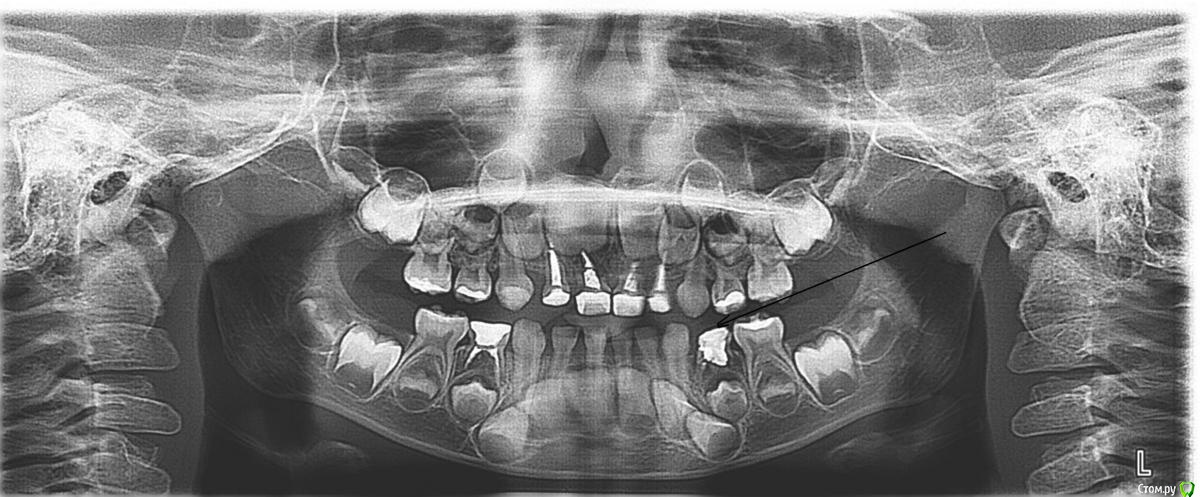

ki_wi Опубликовано 16 января, 2016 Поделиться Опубликовано 16 января, 2016 пришли с ребенком (4,5 года) на лечение зубов к стоматологу. сделали снимок (прилагаю его). посмотрев его, стоматолог говорит, что нижний зуб (я его отметила на снимке черной стрелкой), надо удалять. только я толком и не поняла почему. буду признательна за объяснения и действительно ли его надо удалять. Ссылка на комментарий

Джима Опубликовано 17 января, 2016 Поделиться Опубликовано 17 января, 2016 Э-э-э... А давайте я промолчу Постарайтесь попасть всё-таки к первому вашему врачу и сделать прицел, там лучше будет видно. По-видимому, зубу всё-таки конец, это бывает, когда пульпит лечат в очень раннем возрасте. Это не повод для расстройства, но вам придётся делать распорочку между двумя соседними зубами, чтоб не потерять место для постоянного зуба. 1 Ссылка на комментарий